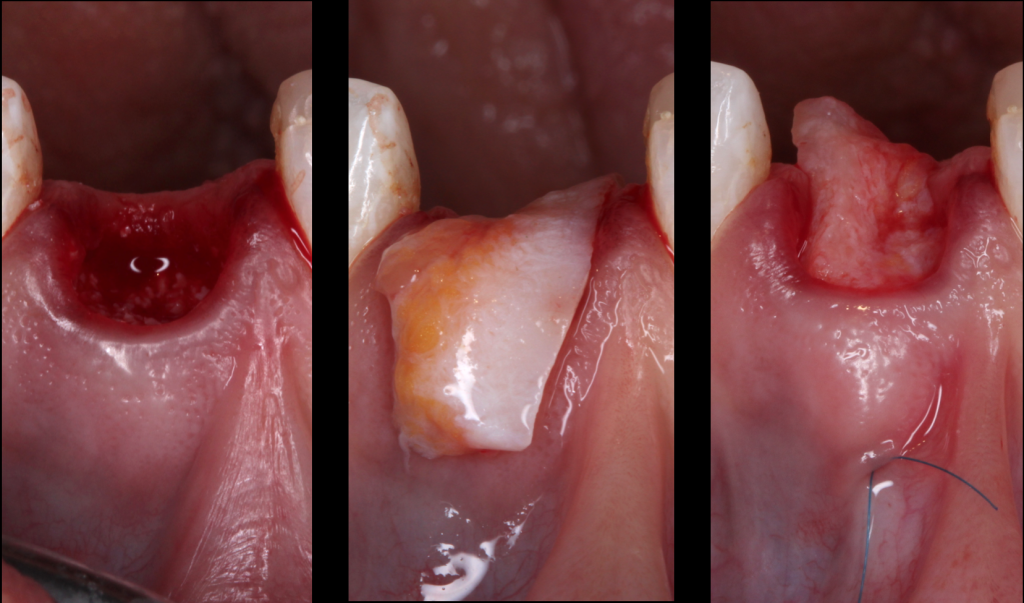

#4. The saddle connective tissue graft

The saddle connective tissue graft associates closure of the extraction site with an increased volume of soft tissues in the buccal part (Chen and Dahlin, 1996).

The graft is positioned in the vestibular and palatal which involves the realization of a buccal supra-periosteal envelope (about 5mm) and a palatal detachment (about 3mm) to introduce the connective graft while preserving the papilla (Fig.5).

The increase in the thickness of the buccal gingiva makes it possible to compensate for the irreversible loss of bone volume despite the filling, and thus to obtain the best horizontal and vertical preservation of the soft tissues (Vanhoutte et al., 2014).

This approach, which is more complex, increases the quantity of soft tissues, particularly in the case of a fine periodontal phenotype, and thus reduces the need for a connective graft during implant placement. Some authors recommend keeping an epithelial area on the exposed part of the graft.